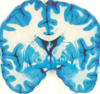

Label 5, 6 & 7

1 - superior temporal gyrus;

2 - inferior frontal gyrus; 3 - insular cortex;

4 - temporal stem;

5 - internal capsule;

6 - thalamus;

7 - lentiform nucleus (the internal and external globus pallidus and the putamen)

8 - frontal horn;

9 - superior circular sulcus;

10 - inferior circular sulcus.